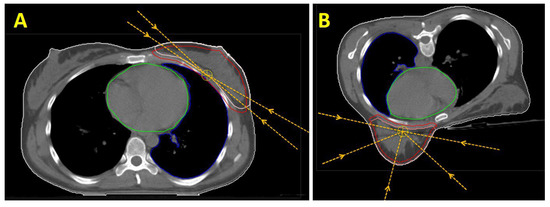

In contrast, for the EBRT of the PTV “B-PSR”, there was no advantage of the prone position over the supine position in our study. In the prone position, gravity pulls the heart ventrally towards the sternum and thus towards the caudal parasternal lymph nodes. This inevitably results in closer proximity of the heart to the PTV and the high-dose area (Figure 2). Consequently, the cardiac dose is higher in the prone position. Even if the difference is not so pronounced for patients affected on the left side due to the left-lateral position of the heart (mean heart dose in the prone position was 7.35 Gy and in the supine position was 6.0 Gy), the effect is considerable for patients irradiated on the right side. Taken together, the supine position results in significantly lower cardiac exposure in the supine position.

Figure 2. CT sections of a patient with left-sided breast cancer: (A) in the supine and (B) in the prone positions. Contours marked are the CTV “B” (light red), the PTV “B” (red), the CTV “PSR” (pink), and the PTV “PSR” (purple). In addition, the OAR “heart” (green) and OAR “left lung” (blue) are depicted.